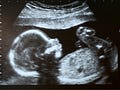

Abortion Worker Told Not to Describe the Baby to People Seeking Abortions

She was warned not to show the ultrasound or give facts about fetal development

When working as a midwife, Carey always showed the ultrasound screen to pregnant people and described their babies to them.

At the abortion facility, however, she was ordered to turn the screen away, and not to give any information about the baby. Carey writes:

When a woman is undergoing an ultrasound scan, ‘Don’t comment on what you are seeing, unless they ask you,’ I was told by the supervising practitioner. Beyond telling patients whether they are under ten weeks pregnant – when you can abort medically with pills at home – I learnt to ask women how much they wanted to see and know.1

When a pregnant person doesn’t want to see an ultrasound or know anything about fetal development, is withholding this information in her best interest?

Many post-abortive people will go on to have children later in life. They will see the new, wanted baby on the ultrasound screen. And if they’ve had a previous abortion, this can be highly traumatizing. Especially when they are caught completely unprepared.

Ultrasound Leads to Post-Abortion Trauma

Therapist Ellie Shumaker, who works with post-abortive people, wrote about one woman, who she calls Kim. Kim had already been through a healing program for a past abortion. She had named her aborted baby Becky, mourned her deeply, and thought she was healed from the trauma.

Years after her abortion, Kim was happily married and expecting another baby. To her and her new husband, the future looked bright. They were looking forward to welcoming their new son or daughter into the world.

But Kim showed up at Shumaker’s office, sobbing, after the first ultrasound of her much-wanted child.

Shumaker quotes Kim:

I was feeling fine. I’d gotten up on the table and they put this thick jelly stuff on my belly and then ran this machine over me. It didn’t hurt… But then that picture came on and wow… It was bad. That feeling took over me, took me by surprise.6

Kim then described the feeling in more detail:

When I first looked at that screen, some kind of a jolt went through me, and not a good jolt. Like a stab. Like sad and kind of anxious too. And that feeling keeps coming back, when I don’t want it too [sic]. This should be the happiest time in my life, finally married to Charles, finally pregnant. I wish like anything that I could be one hundred percent happy but I’m not.7

Kim was filled with doubts about her ability to be a mother, and guilt over Becky’s death.

Kim said, “I wasn’t much of a mother to that baby. What makes me think I can be a good mother to this one? … I don’t deserve to have this baby.”8

Instead of having a happy, positive experience with her loving husband, greeting her new and much-loved baby and joyfully seeing him for the first time, Kim was traumatized and questioning her ability to be a good mother. What should’ve been a happy experience, a milestone in a much-wanted pregnancy, turned out to be an ordeal. Instead of celebrating, Kim was mourning.

And this was someone who had already gone through an abortion healing program and thought she’d come to peace with the loss of her first baby. One can only imagine the shock and distress of a pregnant person who’s never undergone any healing at all.

Kim had to work very hard in therapy to overcome her intense emotions.